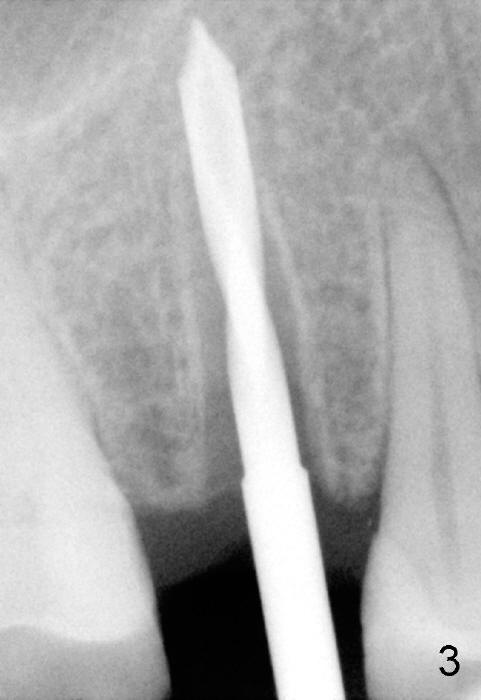

A 51-year-old man has several missing teeth in the maxilla restored by a partial denture. The tooth #4 fractures (Fig.1) and is planned to be restored by an implant (Fig.2 design: 4.5x14 mm). Immediately post extraction, osteotomy is initiated by a 2.0 mm pilot drill at the depth of 14 mm (3 mm into new bone, Fig.3). Finally a 4.5x14 mm SM (submerged) implant is placed with insertion of a 5.2x5(3) mm healing abutment (Fig.4). Mixture of autogenous bone and demineralized cortical allograft is placed in the gap between the buccal plate and the implant/abutment (Fig.6), covered by collagen membrane (Fig.7 M; P: partial denture). In fact the membrane is fixed between the implant and the healing abutment lingually. The wound is finally covered by perio dressing (Fig.5 ^). The patient returns 5 days postop. The perio dressing is removed unintentionally. It appears that the membrane has started to be resorbed (Fig.8).